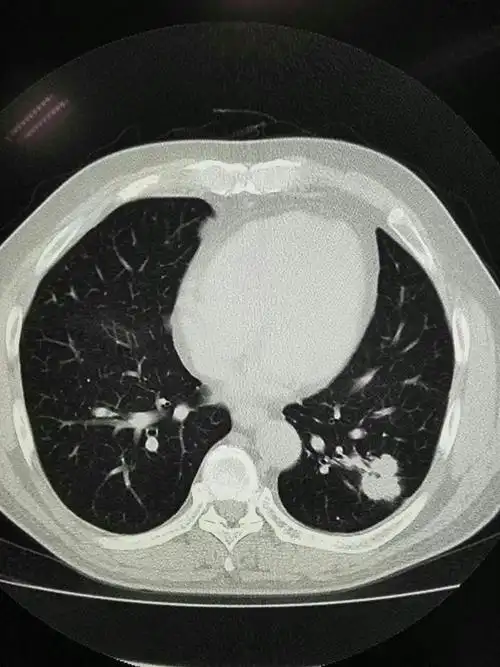

就是咳嗽,胸疼,有时候平躺的时候呼吸困难,但ct发现典型肺结核(图1-2)